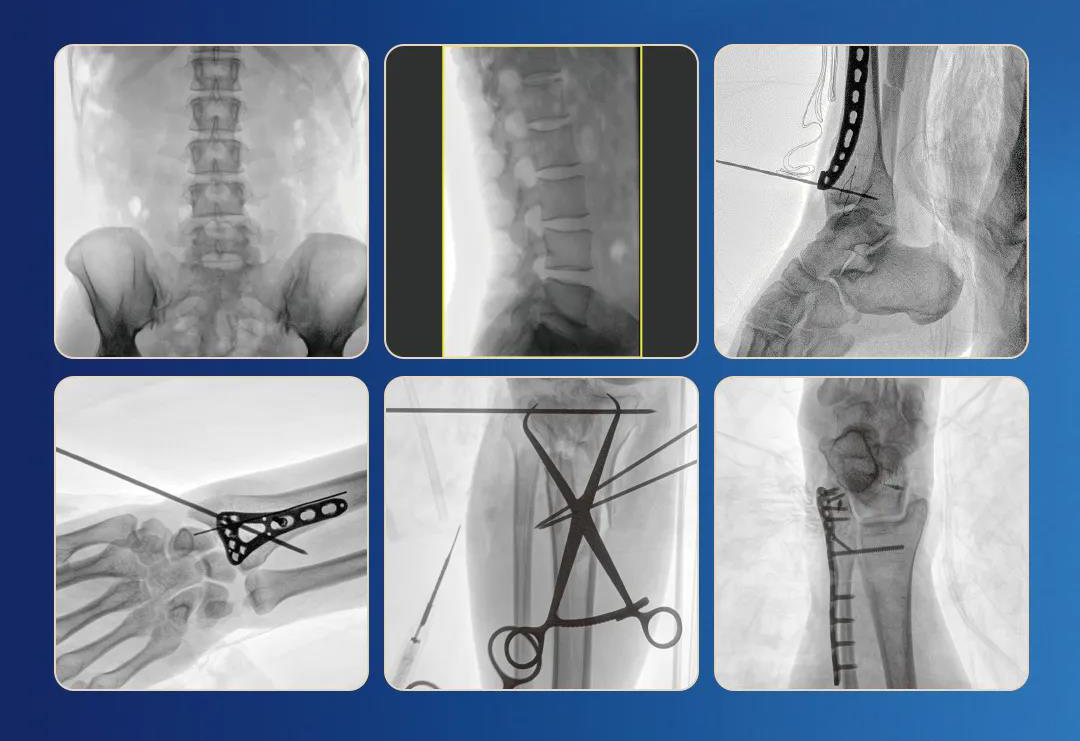

一、臨床應用

1.關節手術

2.創傷手術

3.脊柱手術

4.疼痛治療